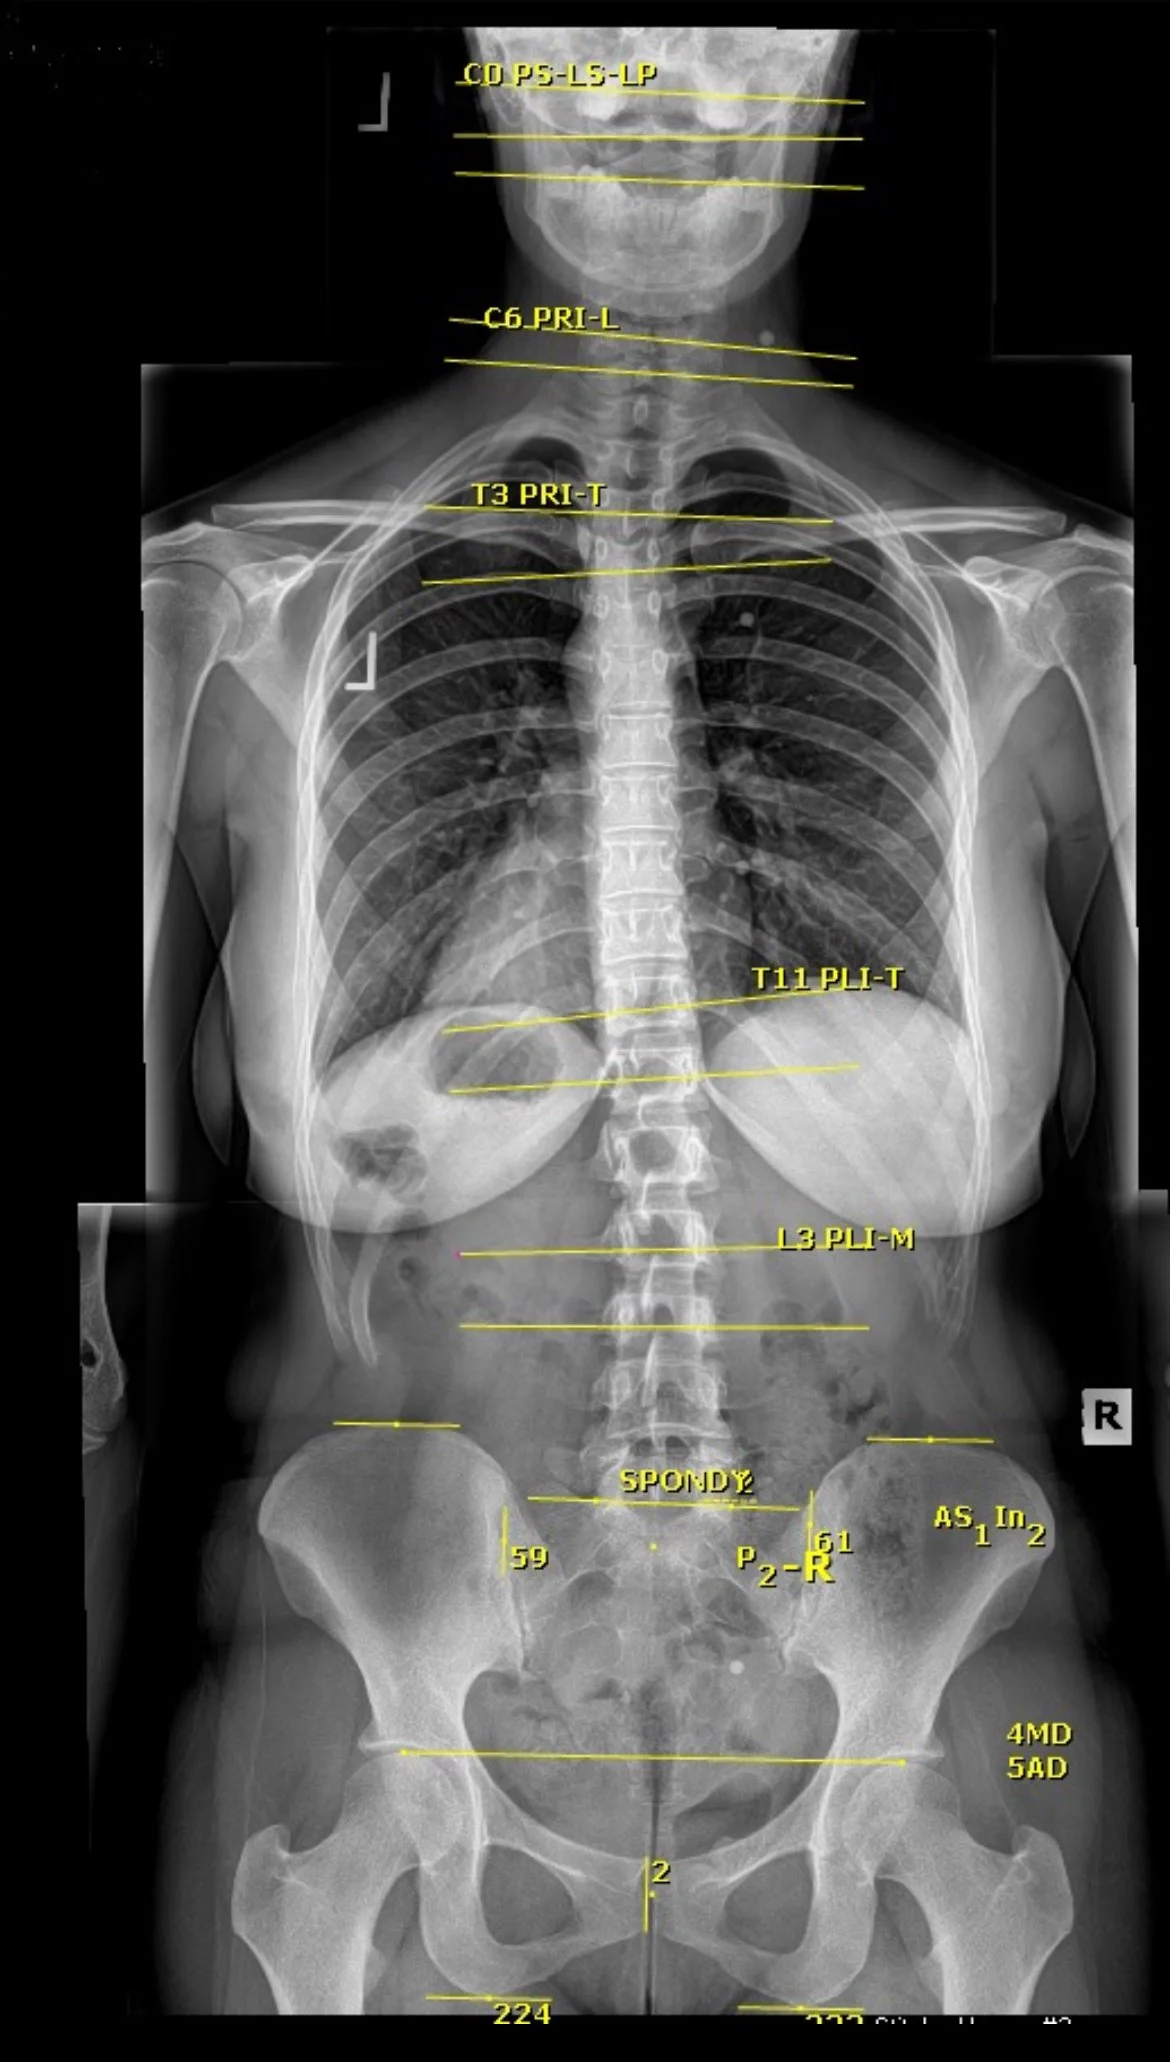

Understanding the exact structure of your spine. This is helpful in evaluating posture, joint and disc health.